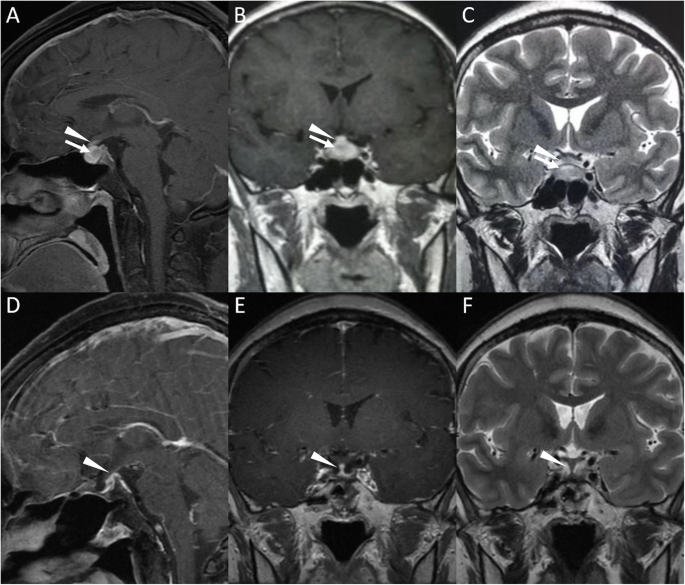

A 40-year-old female with a 4-month history of polydipsia, polyuria, headache, menstrual disorder and fatigue was admitted to the hospital. Examinations revealed a urine osmolality of 63 mOsm/kg when plasma osmolality reached 307 mOsm/kg and serum sodium was 148 mmol/L, and deficiencies of adrenocorticotropic hormone, thyroid-stimulating hormone and gonadotropins. Magnetic resonance imaging (MRI) revealed homogeneous signals in the pituitary gland as well as thickening of the pituitary stalk (Fig. 1), which supported a diagnosis of central diabetes insipidus. FDG PET was performed with a dose of 5.55 MBq (0.15 mCi) per kilogram of body weight to localize the pituitary and/or the pituitary stalk lesions and revealed radioactivity at both sites (Fig. 2). However, the elevated FDG uptake was inadequate for an etiological diagnosis, and FDS (5.55 MBq/kg) was utilized to further explore the nature of the disease. The lesions also showed increased FDS uptake at 30 min and 120 min after FDS injection (Fig. 2), both of which were significantly higher than normal brain uptake. The patient was suspected to have autoimmune or infectious pituitary inflammation based on FDG and FDS activity, and both tracers also excluded possible extracranial involvement.

Contrast-enhanced T1-weighted and T2-weighted MR images of the lesions. a-b. Pituitary with a size of 18.6 mm × 8.2 mm × 9.9 mm displayed a contrast-enhanced signal, and a lesion with a size of 6.5 mm × 5.2 mm × 4.6 mm and a relative hypointense contrast-enhanced signal was located (arrow noted). The pituitary stalk with a size of 5.1 mm × 1.7 mm showed an isointense contrast-enhanced signal (arrowhead noted) compared with the normal pituitary stalk. c. The pituitary lesion presented a hyperintense T2-weighted signal (arrow noted), and the thickened pituitary stalk exhibited an isointense T2-weighted signal in comparison with the normal pituitary. d-f. Contrast-enhanced T1-weighted and T2-weighted MR images of the lesions 3 years after surgery. The pituitary displayed postsurgical changes with no significant hypointense contrast-enhanced signal or hyperintense T2-weighted signal, and the pituitary stalk thickness was reduced (3.0 mm × 2.0 mm, arrowhead noted) compared with pretreatment MRI

Transnasal biopsy was performed for a definitive diagnosis. A lesion was found locating at posterior pituitary, while the anterior pituitary remained normal. Histopathology of the posterior pituitary lesion revealed lymphocyte infiltration and fibrosis of the pituitary gland, while no evidence of malignant elements or infection was seen, which indicated a diagnosis of autoimmune hypophysitis. The patient was then treated with oral prednisone (starting dosage of 40 mg/day, gradually decreased every 3 weeks to a maintenance dosage of 10 mg/day), desmopressin acetate (0.2 mg/8 h) and levothyroxine (50 μg/day) and showed an improvement in clinical symptoms and on radiological examination (Fig. 1). However, hypopituitarism remained stable and hormonal replacement was consistently needed.